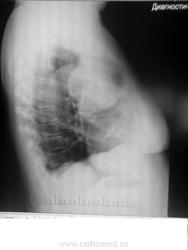

Загадочные кистовидные образования.

Жалобы на одышку. Архив 6 мес назад без данных изменений. Из анамнеза Са МЖ.

Ваши мнения коллеги)

За 6 месяцев это не могло вырасти...Что это? Что-то из средостения?

1.  Mts (но лично мне пока еще не встречались mts таких размеров из МЖ, больше похоже на из ЖКТ)

2. Паразитарные кисты (если учитывать появление в течение 6 мес.)

Метастазы, как по мне....возникновение и рост метастазов находится под значительным влиянием эндогенных факторов. Молодой возраст, гормональные сдвиги в сторону гиперэстринизма, беременность и лактация, а возможно и нейротрофические влияния способствуют развитию метастазов. Несомненную роль в ускорении появления и роста метастазов могут оказать и экзогенные факторы: травма опухоли при массаже и неполноценной операции, ультрафиолетовое облучение и неоправданно длительное введение эстрогенных препаратов.....

Такую картинку могла дать и саркома лёгкого, но не за 5 месяцев. На мой взгляд, имела место "хрень" с архивом, или перепутали, или аналогичное...

Помеченная стрелками "полутень", также видна только в одной проекции

на саркому можно было бы подумать.если бы не было такого же шарика в S9-10 cлева. А тень-"полутень" слева в в\поле более мягкой по интенсивности выглядит потому,что  и снимок с разворотом (и левое легкое чернее) и общее равномерное снижение пневматизации легочной ткани правого легкого- что-то (mts?) мешает норм. вентиляции на уровне правого главного бронха.

И, вот под влиянием Добрынина и "тойного" синего тумана, сам-собой напрашивается

паскудный вопрос о добропорядочности восходящего отдела грудной аорты. Ведь эта

тенюха, что на прямой, что на боковой очень интимно связана с тенью восходящей аорты, да и контура (самостоятельного) восходящего отдела не видно, даже не угадывается... - сплошной туман. Вопрос к автору - ТРАВМА ГРУДНОЙ КЛЕТКИ У ПАЦИЕНТА БЫЛА?

а паразитарное сразу со счетов сняли?)

Вам не кажется что верхний контур образования правого легкого нечеткий и образован несколькими более мелкими фокусами?

Можно думать только о гидатиде, но, чтобы так гидатида, за указанный срок, подросла, то её нужно было кормить анаболиками...